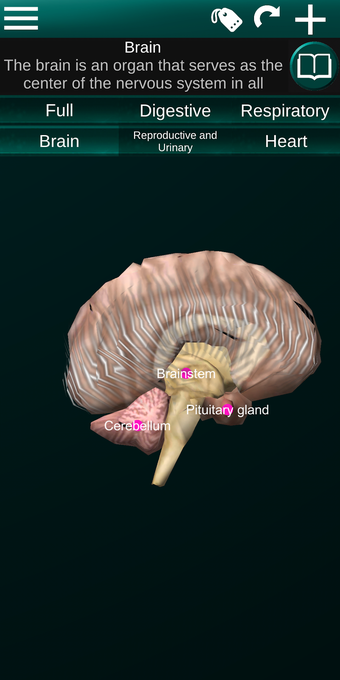

Diese Anwendung zeigt ein dreidimensionales Modell der menschlichen Körperorgane und eine Beschreibung aller von ihnen.

Sie können jedes Organ wie Herz, Gehirn, Lunge, Fortpflanzungssystem, Leber, Darm, Eierstock, Hoden, Magen, Niere usw. anfassen.

Sie ist für alle Menschen nützlich, auch für Studenten, da jedes Anatomieorgan in einer anderen Farbe dargestellt ist.

Sie können die App verwenden, um herauszufinden, welches die verschiedenen Körperorgane sind und welche Funktionen sie haben.